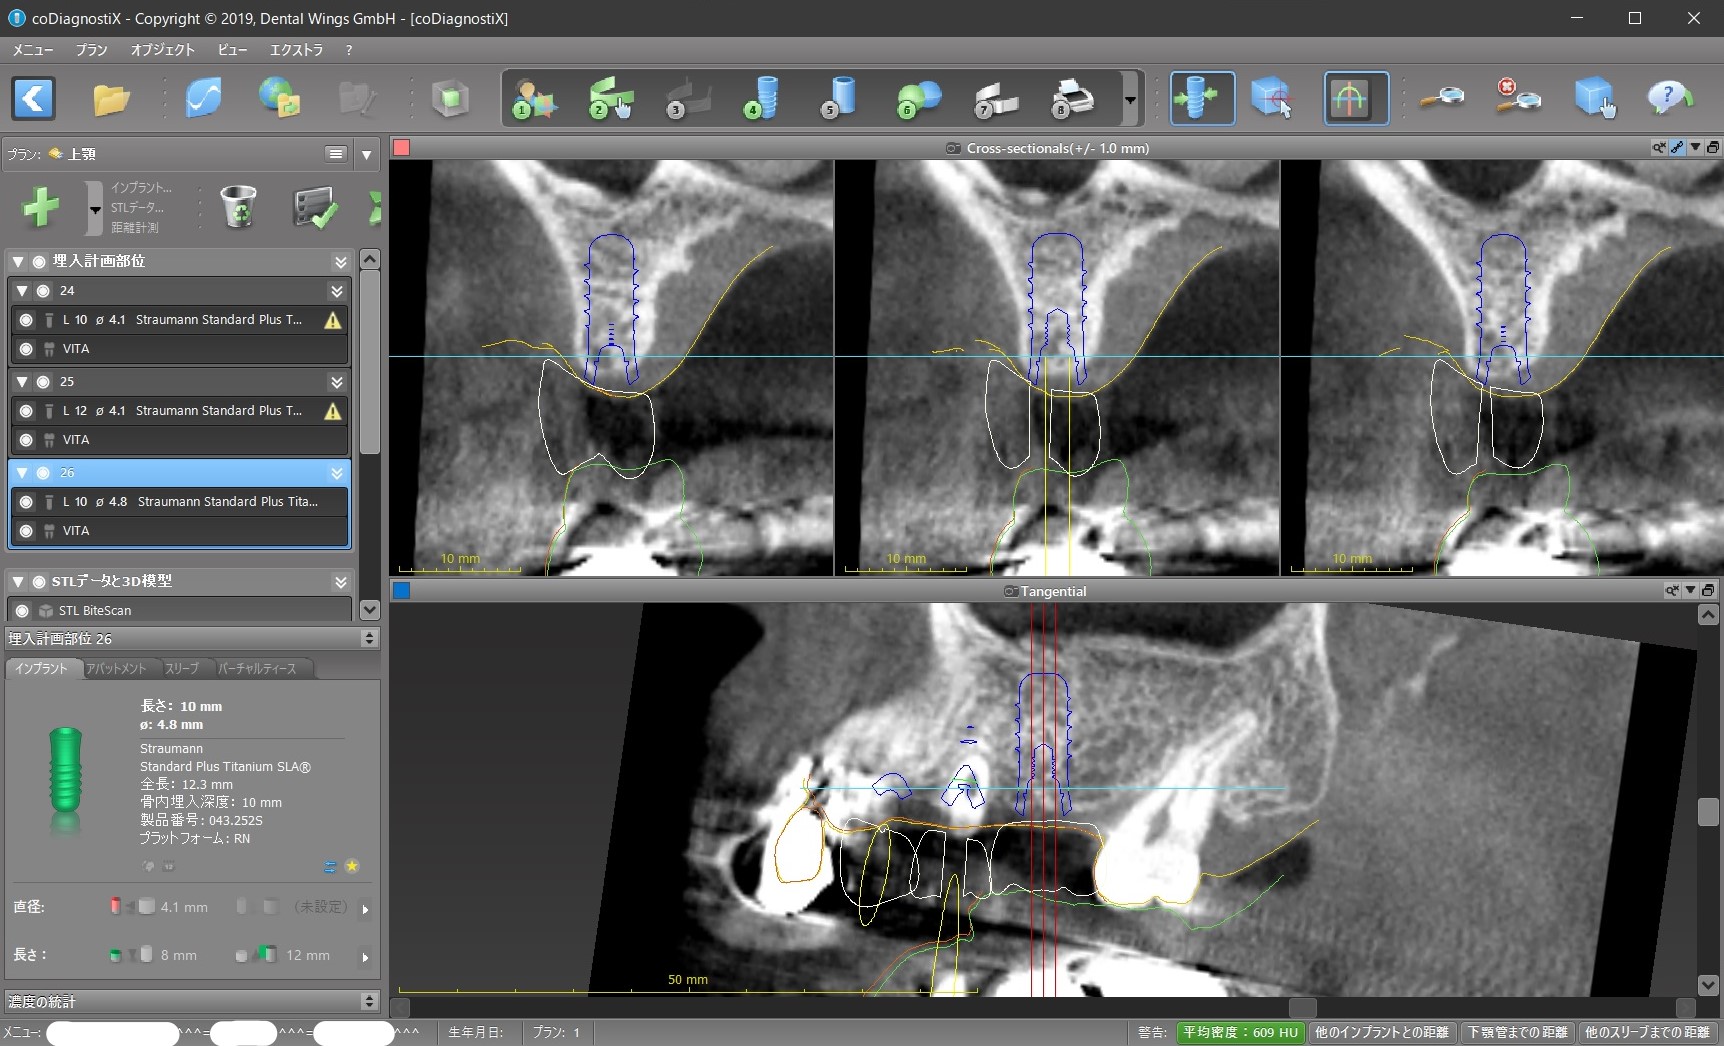

インプラントの位置のシュミレーション

今回で言えば、インプラントを前から順に#24、#25、#26と呼ぶと

① #24がその前の天然歯に当たって、そもそもこの位置に入れられない。

② 前述のように#24上部構造が下の歯と咬まない。ちゃんと咬むようにするためには矯正治療が必要になる。

③ #24のインプラントと上部構造との間に角度を付けるか、もしくはGBR(骨を増やす、作る処置)が必要になる。

④ #25インプラント部位に歯の根が残っているので、これをインプラント手術の時に取り除くのと同時にそこに骨を増やす処置が必要になる。

今回、④の問題は対応が優しく、#25、#26部位はインプラントを入れる条件がかなり良いため、#24にはインプラントを入れずに#25と#26にだけインプラントを入れて、それを土台としたインプラントブリッジの設計にして、#24が下と咬まないことはご了承して頂くか矯正治療をするか相談するということになります。